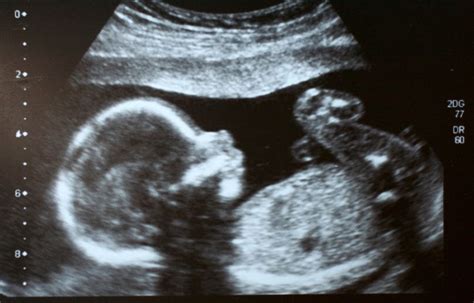

Das zweite Trimester: Ausgeprägtere Merkmale und Bewegungen

14. Schwangerschaftswoche: Entwicklung der Mimik und Geschlechtsbestimmung

In der 14. Schwangerschaftswoche entwickelt sich die Mimik des Babys weiter. Stirnrunzeln, Grimassen schneiden - all das ist ab jetzt möglich. Vielleicht lässt sich auch das Geschlecht des Babys schon erkennen. Die Geschlechtsbestimmung findet aber meist bei der zweiten Ultraschalluntersuchung zwischen der 19. und der 22. Schwangerschaftswoche statt. Auf einem Ultraschallbild kann man bei Zwillingsschwangerschaften zwei Fruchtblasen sehen.